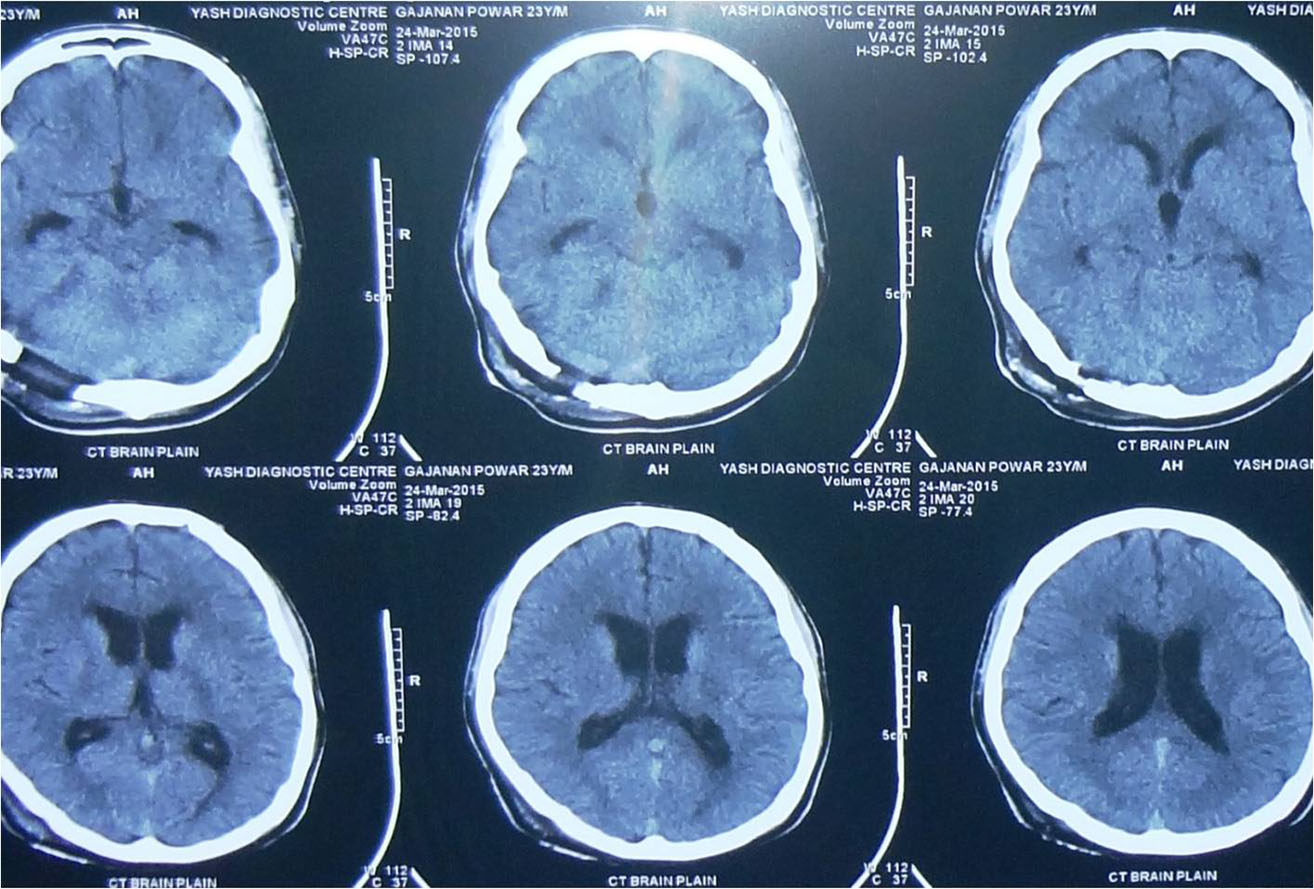

any of these symptoms he/ she should consult a neurosurgeon immediately. Usually CT Scan/ MRI of brain help

in the diagnosis. Most of the brain tumours can be safely treated by surgery but the treatment plan may vary